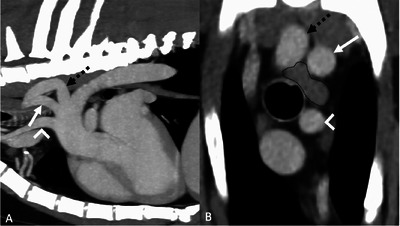

Aberrant right subclavian arteries (ARSAs) are a form of vascular ring anomaly (VRA) in dogs and the most common VRA in people. To date, there has been no large-scale study on ARSA in dogs and their potential clinical significance. For part one, a single-center retrospective observational study was performed to determine the prevalence of ARSAs in a population of 1000 dogs undergoing contrast-enhanced CT for various reasons. For part two, further canine ARSA cases were collected to characterize their imaging features further and determine whether any imaging findings were more frequent in dogs with clinical signs attributed to a VRA. The prevalence of ARSA was 1.2% (12/1000). For part two, out of a total of 37 dogs with ARSA, this finding was thought to be incidental in 28 cases (75.6%), clinically relevant in 1 case (2.7%), and potentially relevant in 8 cases (21.6%). Cranial esophageal dilation with gas and fluid and esophageal compression at the site of the ARSA crossing the esophagus was found in the case where the ARSA was considered relevant. Esophageal dilation with esophageal compression by the ARSA was also more frequent in the potentially relevant group. Our study shows that an ARSA is more likely to be an incidental finding; however, due to the low number of cases where the ARSA was considered relevant, no specific imaging findings were found that could help determine their clinical relevance.